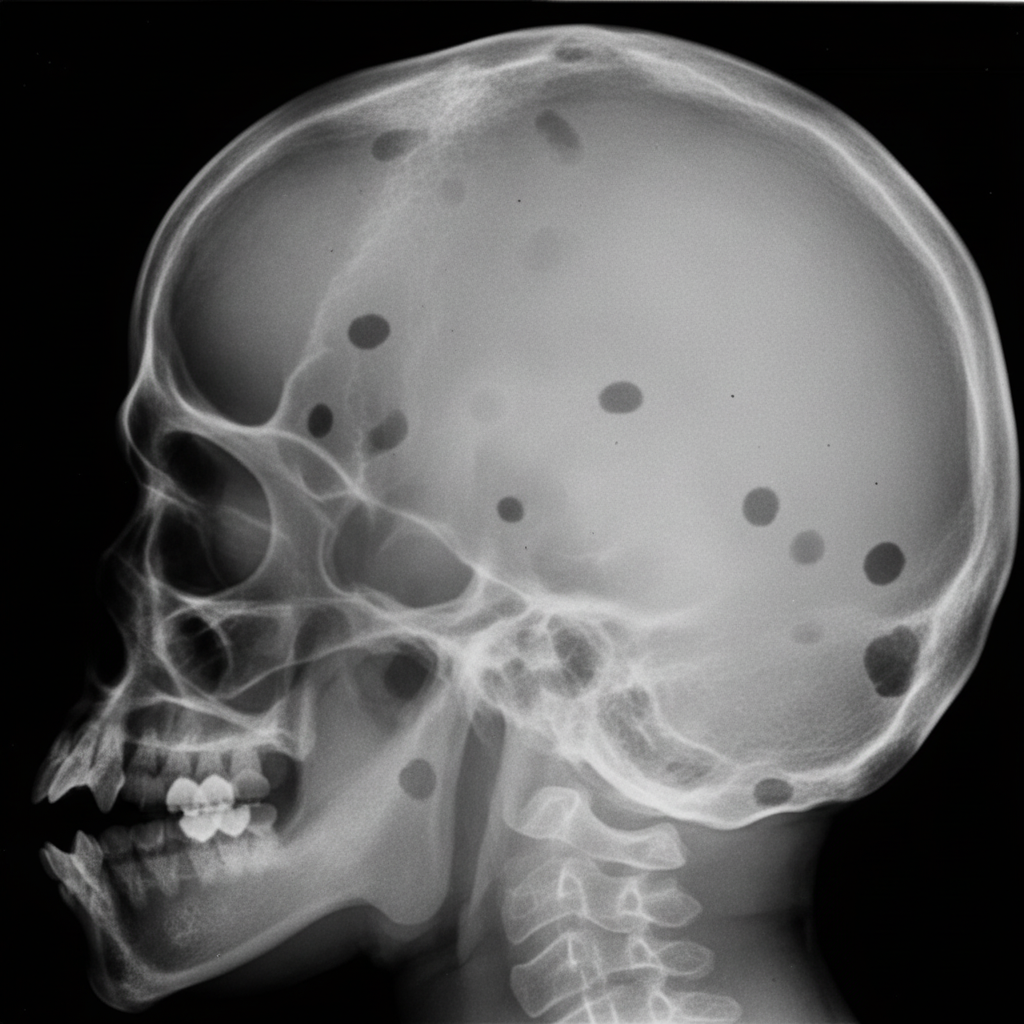

Which of the following conditions is NOT characterized by the radiographic abnormality shown in the X-ray skull?

Explanation: ***Paget's disease*** - Paget's disease characteristically shows a **cotton-wool appearance** or **osteoporosis circumscripta** pattern on skull X-rays, not punched-out lytic lesions. - The radiographic pattern involves **mixed lytic and sclerotic changes** with bone thickening, distinctly different from the discrete lytic lesions shown. *Multiple Myeloma* - Multiple myeloma classically presents with **punched-out lytic lesions** without sclerotic borders on skull X-rays. - These lesions result from **plasma cell infiltration** causing bone destruction and appear as well-defined radiolucent areas. *Histiocytosis X* - Histiocytosis X (Langerhans cell histiocytosis) produces **punched-out lytic skull lesions** with sharply defined margins. - The lesions often have a **beveled edge** appearance and can occur in multiple sites throughout the skull. *Hyperparathyroidism* - Hyperparathyroidism causes **salt-and-pepper skull** appearance with multiple small lytic lesions throughout the calvarium. - The **subperiosteal bone resorption** and generalized osteopenia create a pattern of diffuse lytic changes in the skull bones.